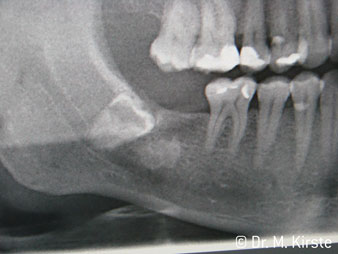

45° ъгъл на наконечника е специално избран поради неговата широка гама от предимства. Колеги, които работят хирургия, и за които този наконечник е главно създаден, скоро ще оценят възможността за ефективна работа в силно ограничени пространства. При екстрахиране на мъдреци, в частност (фиг. 2), няма нужда от голямо разширяване на меката тъкан в областта на бузата (фиг. 3). Дизайнът на главата на наконечника, в съчетание с лекото завъртане на главата по време на препарация, позволява бърза и безопасна работа в ретромоларната област.

Фиг. 2